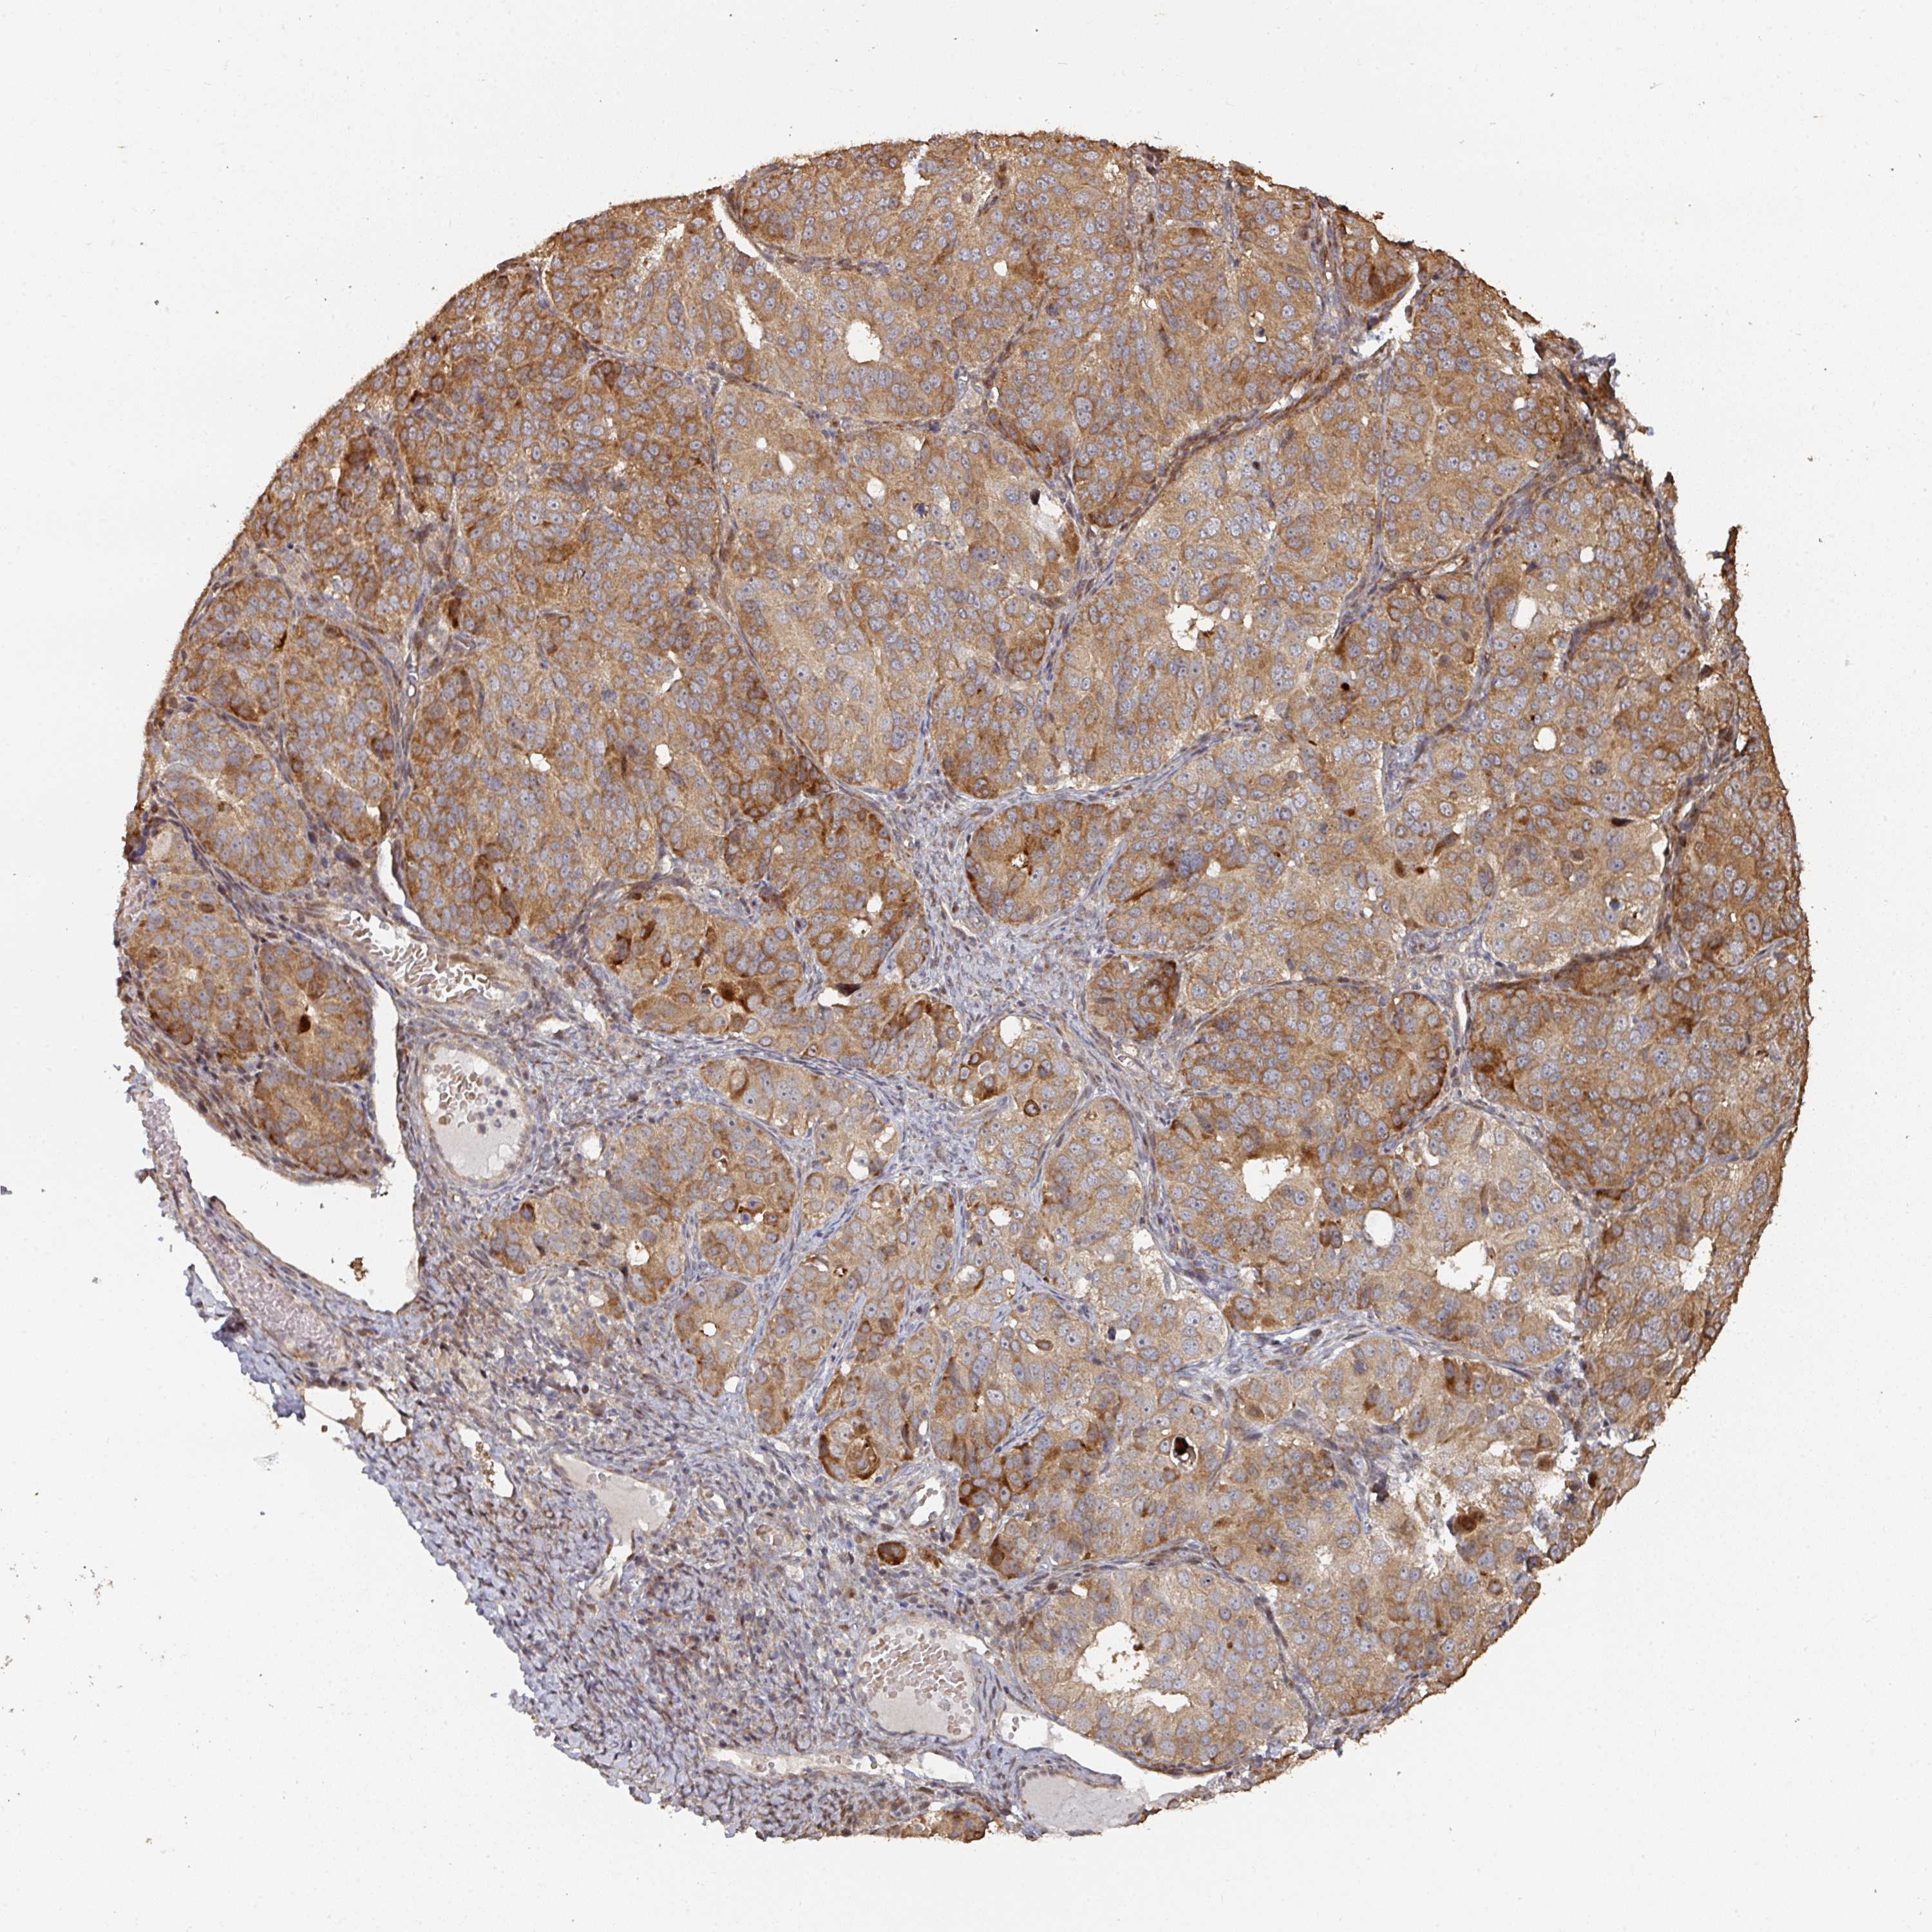

OVARIAN CANCER - Protein expressioni

A mouse-over function shows sample information and annotation data. Click on an image to view it in a full screen mode. Samples can be filtered based on level of antibody staining by selecting one or several of the following categories: high, medium, low and not detected. The assay and annotation is described here.

Note that samples used for immunohistochemistry by the Human Protein Atlas do not correspond to samples in the TCGA dataset.

Antibody stainingi

Antibody staining in the annotated cell types in the current human tissue is reported as not detected, low, medium, or high, based on conventional immunohistochemistry profiling in selected tissues. This score is based on the combination of the staining intensity and fraction of stained cells.

Each image is clickable and will lead to virtual microscopy that enables deeper exploration of all samples and also displays staining intensity scores, fraction scores and subcellular localization as well as patient and tissue information for each sample.

Antibody HPA047237

Staining

High

Medium

Low

Not detected

Intensity

Strong

Moderate

Weak

Negative

Quantity

>75%

75%-25%

<25%

None

Location

Nuclear

Cytoplasmic/membranous

Cytoplasmic/membranous,nuclear

Cystadenocarcinoma, serous, NOS

Carcinoma, endometroid

Cystadenocarcinoma, mucinous, NOS

Carcinoma, NOS